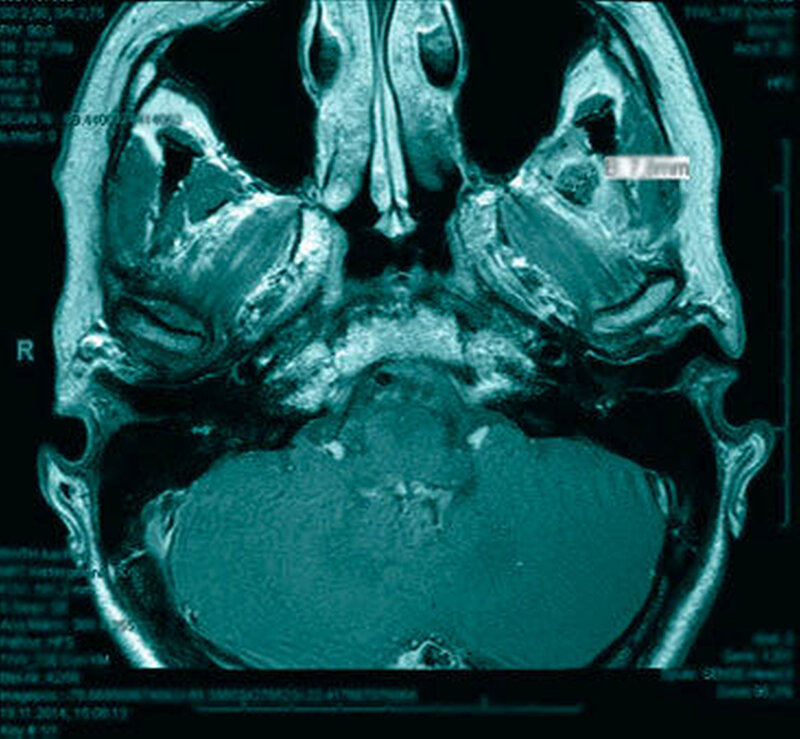

Das neun Tage später durchgeführte MRT zeigte keinen Anhalt für eine Läsion des Diskuskomplexes beidseits. Es wurde jedoch eine umschriebene, teils T2-hyperintense sowie kräftig randständig kontrastmittelaufnehmende Läsion im M. pterygoideus medialis links (axial bis zirka 1,0 cm) angrenzend an den Processus muscularis vereinbar mit einem kleinen intramuskulären Abszess beschrieben (Abbildungen 2 a und b). Des Weiteren erschien der M. pterygoideus medialis links in seinem ganzen Verlauf ödematös verändert, jedoch ohne Anhalt für eine Beteiligung der umliegenden Strukturen wie dem M. pterygoideus lateralis.